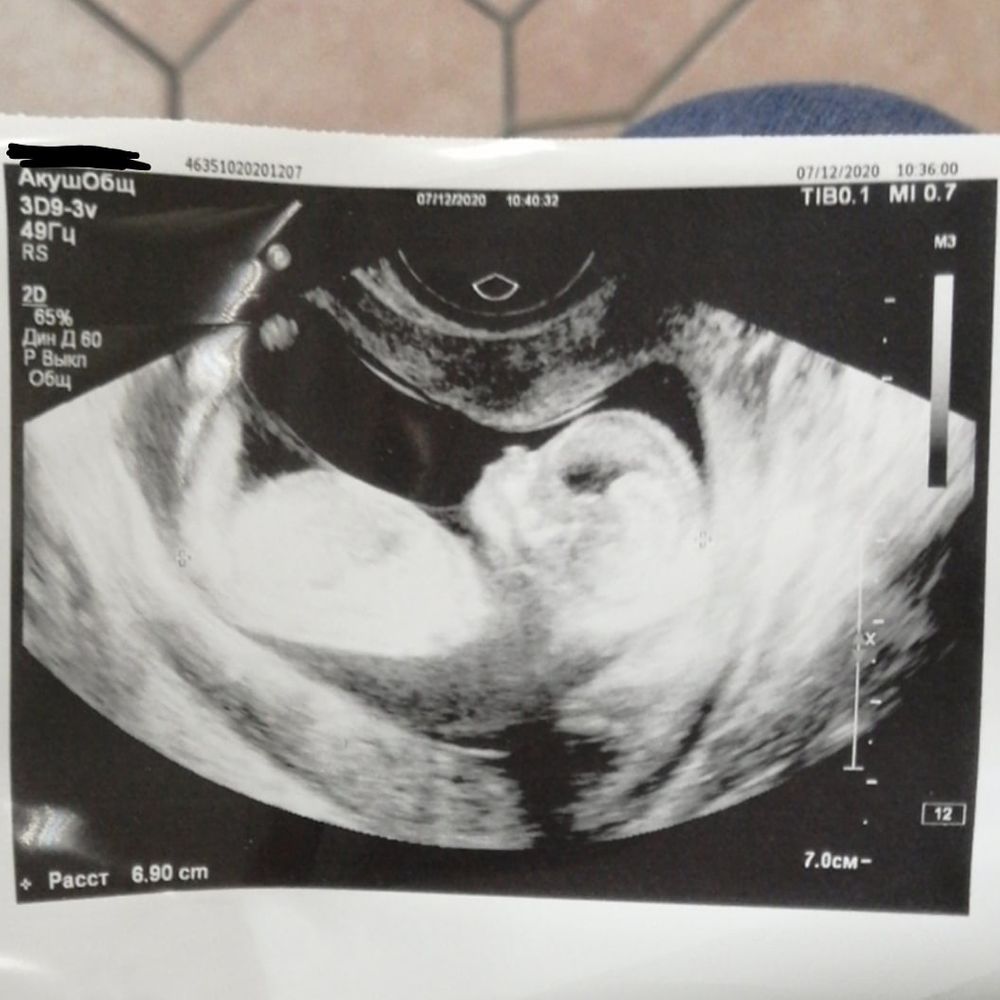

Какой пол на снимке узи?)

Малыш прелесть, лёгких вам родов и здоровья! Но я ничего не вижу( в смысле место это не показано)

Нужного места нет на снимке =(

На снимке ребенок. Половые органы находятся между ног. Или по форме черепа гадать?

Пол рассматривают с позиции низа ножек и попы, тут вообще ничего не понятно. Если вам срочно пол надо узнать сдайте кровь в инвитро на определение пола

Так засвечено все)) Не виден половой бугорок)) Томитесь ожиданием) У меня на скрининге так вертелся и кувыркался, что тоже даже намека на пол не увидели)) Теперь только на второй скрининге узнаем, если не откажется позировать)

по силуэту ребенка пол не ставится)

Это попа)))

На снимке ребенок.))) Более ничего не видно.